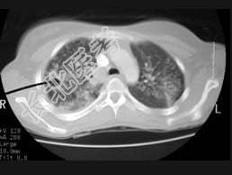

- 单项选择题女,18岁, 1年前患肺结核经抗结核治疗后好转,现发热、咳嗽、体重下降, 结合CT图像,最可能的诊断是 ( )

A、肺结核

B、肺炎

C、肺脓肿

D、肺转移瘤

E、细支气管肺泡癌